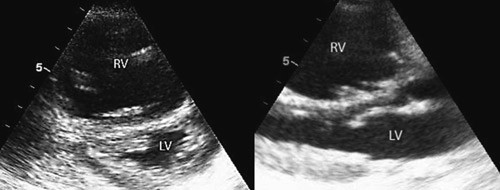

Ved overflytting til lokalsykehuset viste ekkokardiografi normale dimensjoner på alle kamre, god kontraktilitet av venstre ventrikkel (fig 4), noe paradoks bevegelse av septum, ingen trikuspidalinsuffisiens, lett redusert funksjon av høyre ventrikkel bedømt ut fra vevsdopplerundersøkelse av trikuspidalannulus (grenseverdier).